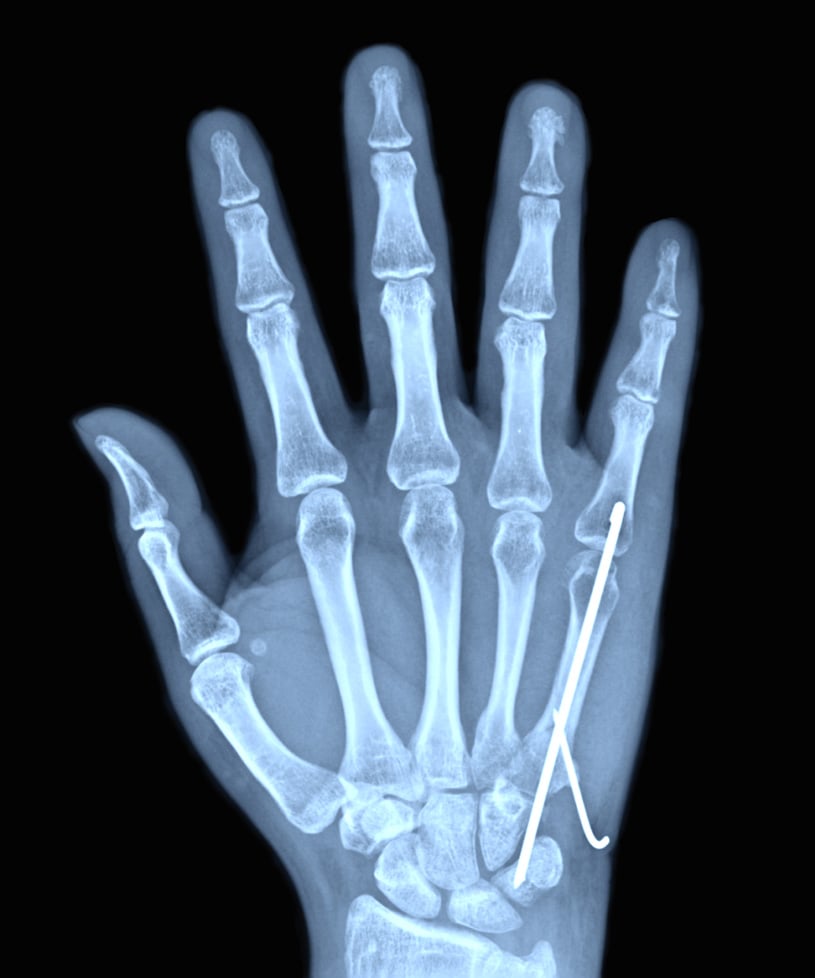

X-ray showing pinning to repair a Metacarpal Fracture

Operative treatment: Surgical repair of metacarpal fractures is required when the fracture pieces are unstable (won’t stay in place), or not healing properly with cast treatment. We perform a regional block to numb the arm, and if the metacarpal can be set straight, we place metal wires through the skin and into the bone to keep it straight while it is healing. If the fracture is severe, we may need to make a small incision over the back of the hand to restore the alignment of the broken metacarpal directly and hold the pieces in place with tiny metal plate and screws. Sometimes, a second surgery is performed after the bone has healed to remove the plate and screws if they are uncomfortable under the skin or cause stiffness.